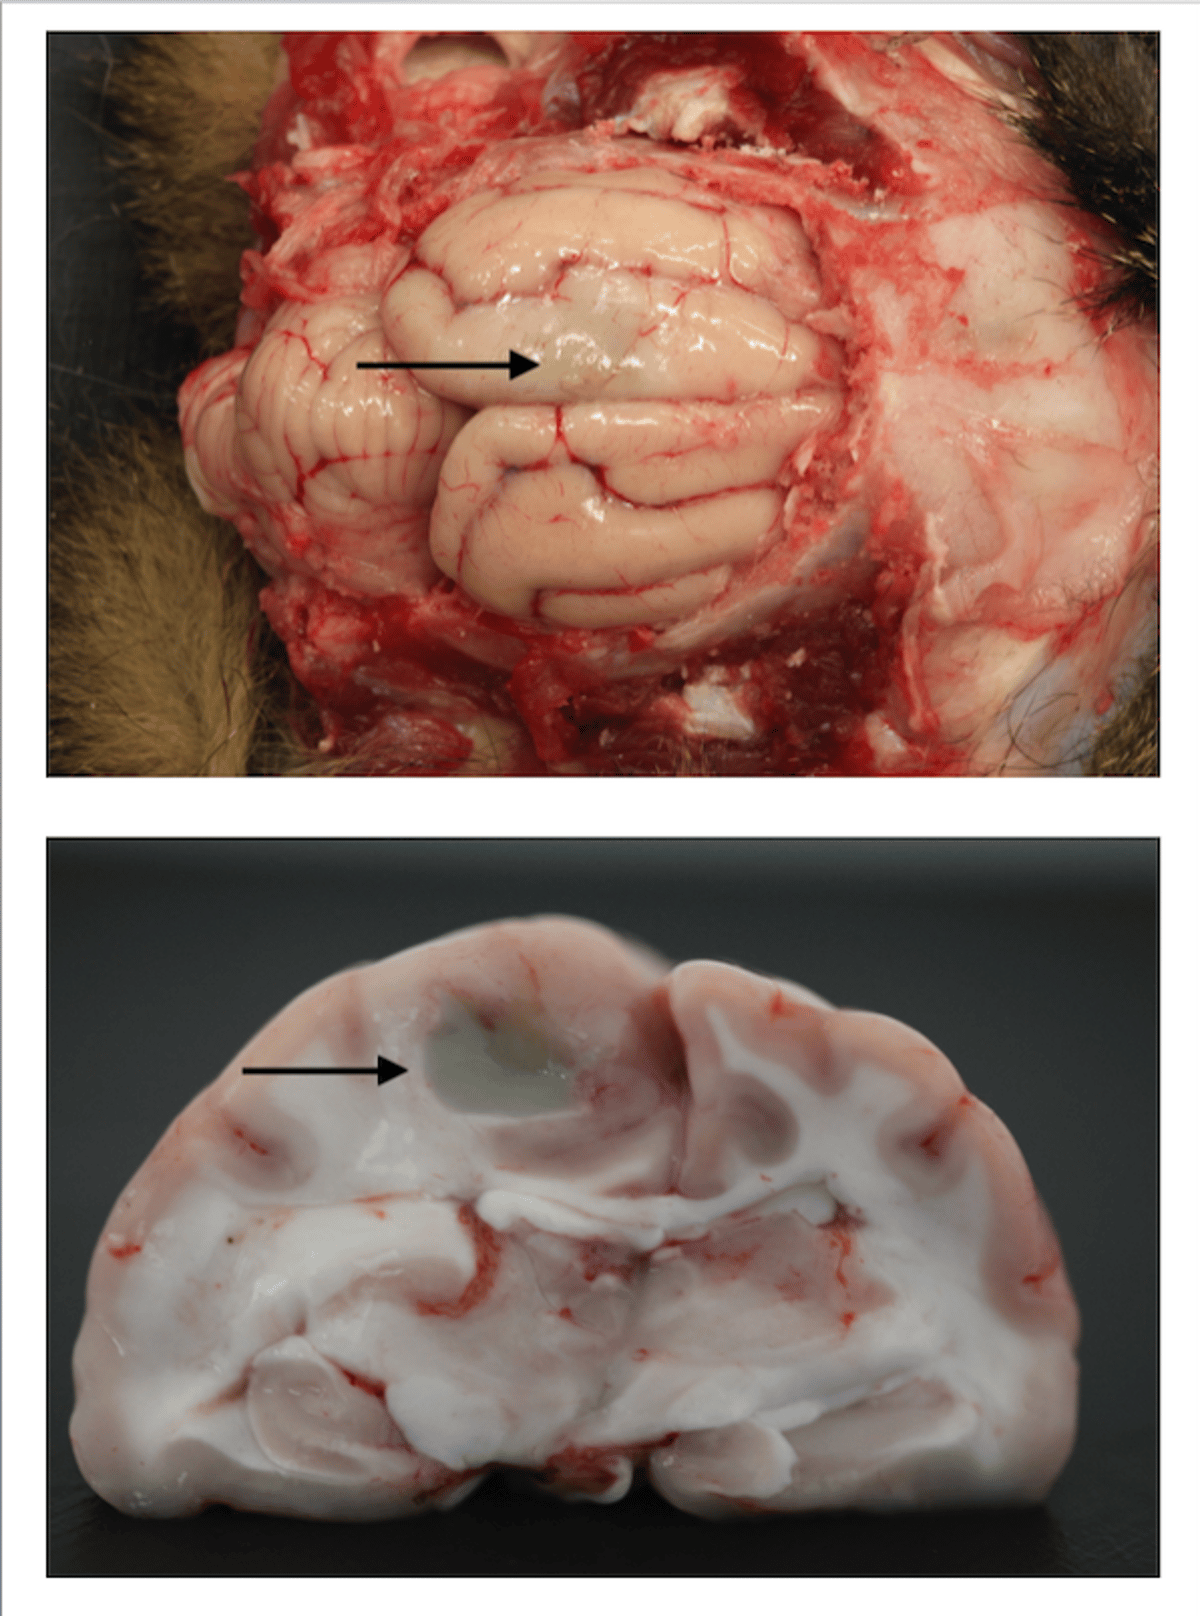

Vistas de los hemisferios cerebrales con herida punzante, gato

Vista superficial (superior) y transversal (inferior) de los hemisferios cerebrales de un gato que revela un proceso supurativo inducido por una herida punzante en el cráneo, que se especula con que se debe a una mordedura de gato.

Cortesía de Brian Cloak.